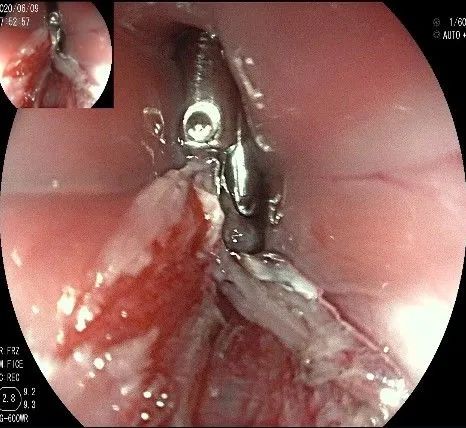

在食管腔内,瘤体的两侧行粘膜下注射后,在瘤体顶部纵向自口侧向肛侧切开食管粘膜。

向下一直切开至齿状线处,白色为鳞状上皮,红色为腺上皮,颗粒样的部分,就是炎性息肉。切开后可见瘤体为白色,表面有血管网,质地较韧。

沿切开的边缘,从口侧开始向下进行粘膜下剥离,剥离的间隙是瘤体之上粘膜之下,期间反复进行粘膜下注射。

随着剥离的进行,瘤体与周围组织的关系越来越清晰。

此时瘤体基底部已暴露出来,起源于固有肌层。

这是最后的“根”部。

换用IT刀可以轻松剥离,又避免切入过深造成穿孔。

剥离接近完成,最后连接的薄层组织。